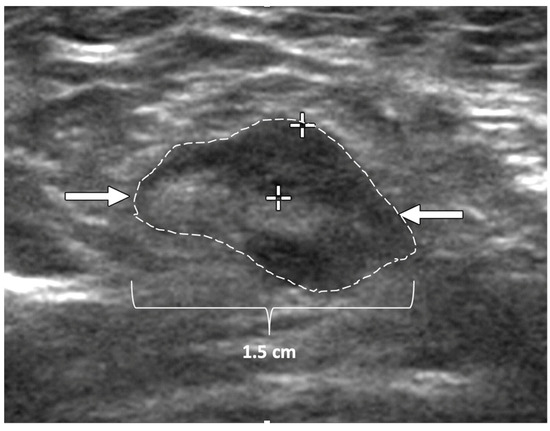

Ultrasound of the breast. Office-based cryoablation is optimized for treatment of ultrasound-visible breast cancers. Consequently, breast ultrasound should be performed of all suspicious imaging abnormalities to assess eligibility for ultrasound-guided cryoablation. Ultrasound permits assessment of the cancer’s proximity to the overlying skin and underlying chest wall and also enables detection of changes in adjacent tissue architecture (e.g., edema, tissue distortion, extension of tumor into adjacent ducts) and could indicate the presence of more extensive disease that would need to be incorporated into the treatment plan (Figure 2). Proximity (<5 mm) of a cancer to the skin is generally regarded as a contraindication to cryoablation, but a safe skin distance can sometimes be created using hydrodissection or injection of saline between the tumor and overlying dermis.

Figure 2.

(A) shows dark, dominant, irregular mass encircled by hash marks with intraductal tumor extensions (dark bands bracketed by paired arrows) extending from left and right sides of dominant mass. (B) shows dark, irregular dominant mass (arrow) surrounded by peri-tumoral edema outlined by hash marks.